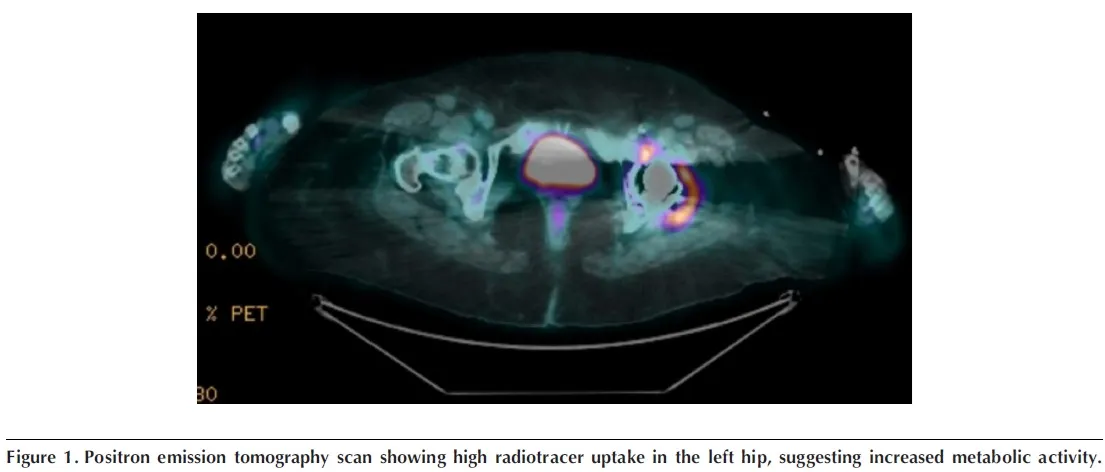

O **PET-CT** (imagem abaixo) revela hipercaptação no quadril operado, adenopatia ilíaca e foco nodular em reto abdominal: inflamação “acendendo” onde houve vazamento de cimento. O filme mental começa a focar: **reação sarcoide-like induzida por adjuvante?**

* **Imagem com mapa da inflamação**: PET-CT positivo no sítio da prótese e cadeias linfáticas adjacentes.

* ECA elevada e PET “quente” próximo à prótese apoiam granulomatose.